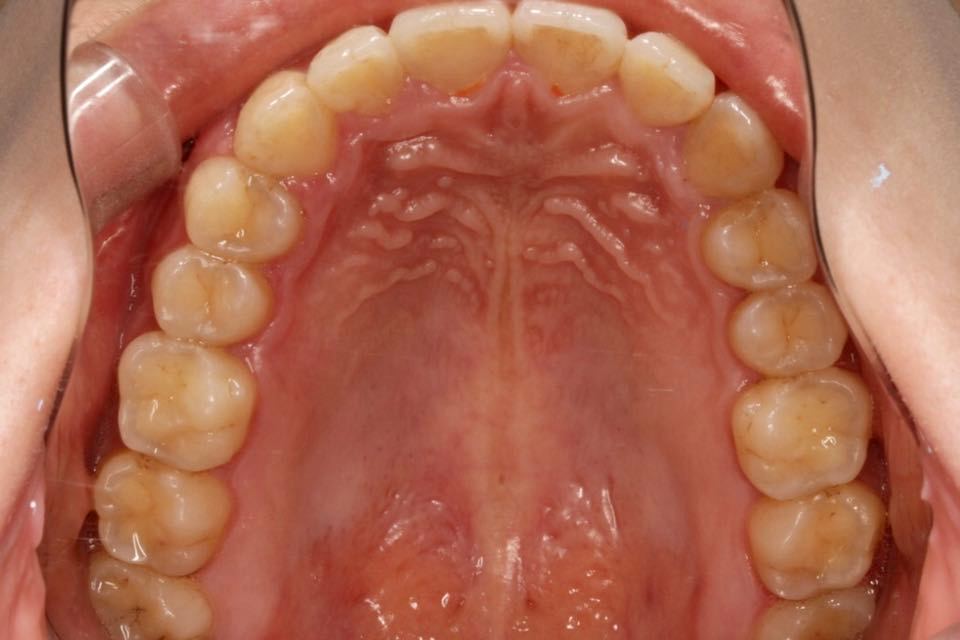

矫正前口内照:

口内:恒牙列,牙列拥挤(中度)。上下颌牙弓呈方圆型。左右对称。右侧磨牙近中性关系,左侧磨牙近中关系,右侧尖牙远中关系,左侧尖牙远牙中性关系。上颌中线偏右2mm,下中性居中。

上颌中线向患者左侧调整,上下颌中线对齐,扩弓加邻面去釉。

治疗改善:关闭散隙,调整中线。

目前阶段:全口牙齿排列整齐,中线居中。前牙覆合覆盖正常,尖磨牙关系达I类咬合关系。总疗程约18个月。